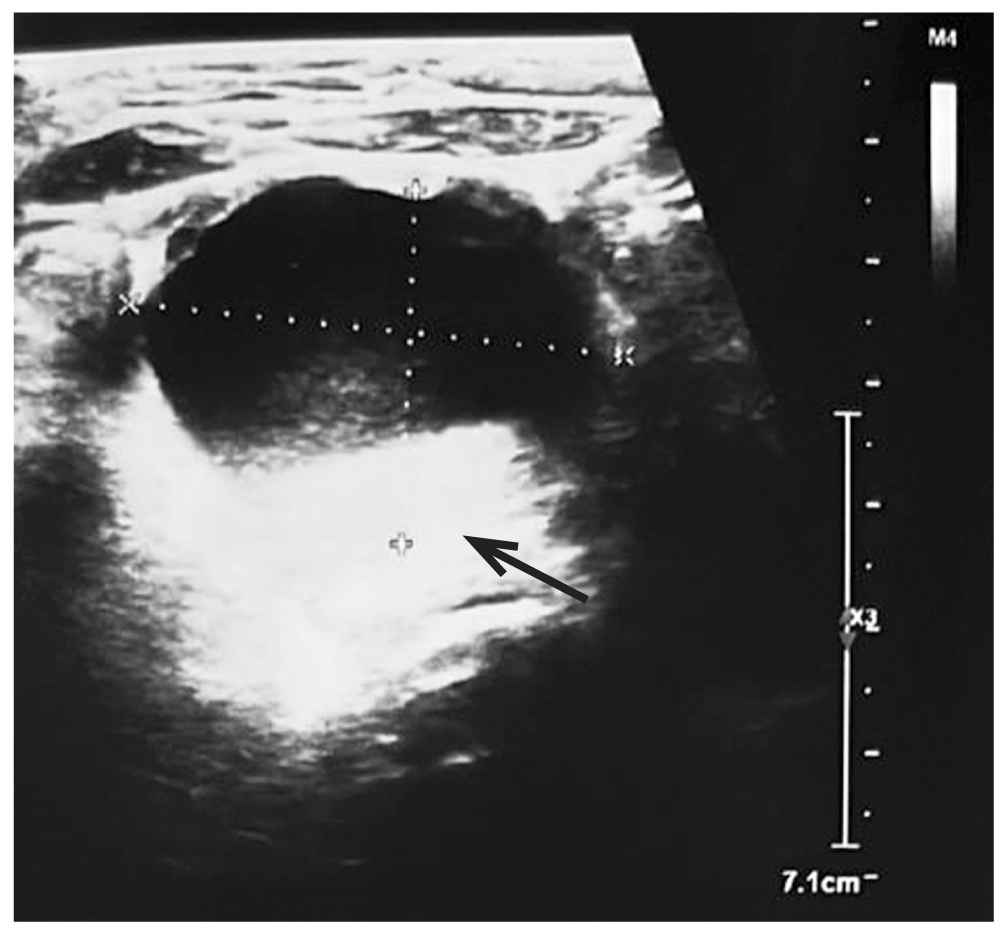

После дообследования 12.04.2022 в возрасте 4 мес. 10 дней выполнена лапароскопия. При ревизии брюшной полости слева определялась киста грязно-серого цвета размерами около 40×30 мм (рис. 2).

Рис. 2. Интраоперационное изображение кисты.

Fig. 2. Intraoperative cyst image.

Неизменённая матка визуализировалась в типичном месте. Левый яичник находился за маткой (цвет белесоватый, не увеличен), маточная труба и фимбрии не изменены. Правый яичник и маточная труба отсутствовали, произошла самоампутация кистозно изменённого правого яичника с маточной трубой, которые подпаялись к сигмовидной кишке (рис. 3).

Рис. 3. Визуализация органов малого таза: 1 — киста, 2 — матка, 3 — левый яичник, 4 — долженствующее место правого яичника и маточной трубы, 5 — сигмовидная кишка.

Fig. 3. Visualization of the pelvic organs: 1 — cyst, 2 — uterus, 3 — left ovary, 4 — the proper place of the right ovary and fallopian tube, 5 — sigmoid colon.